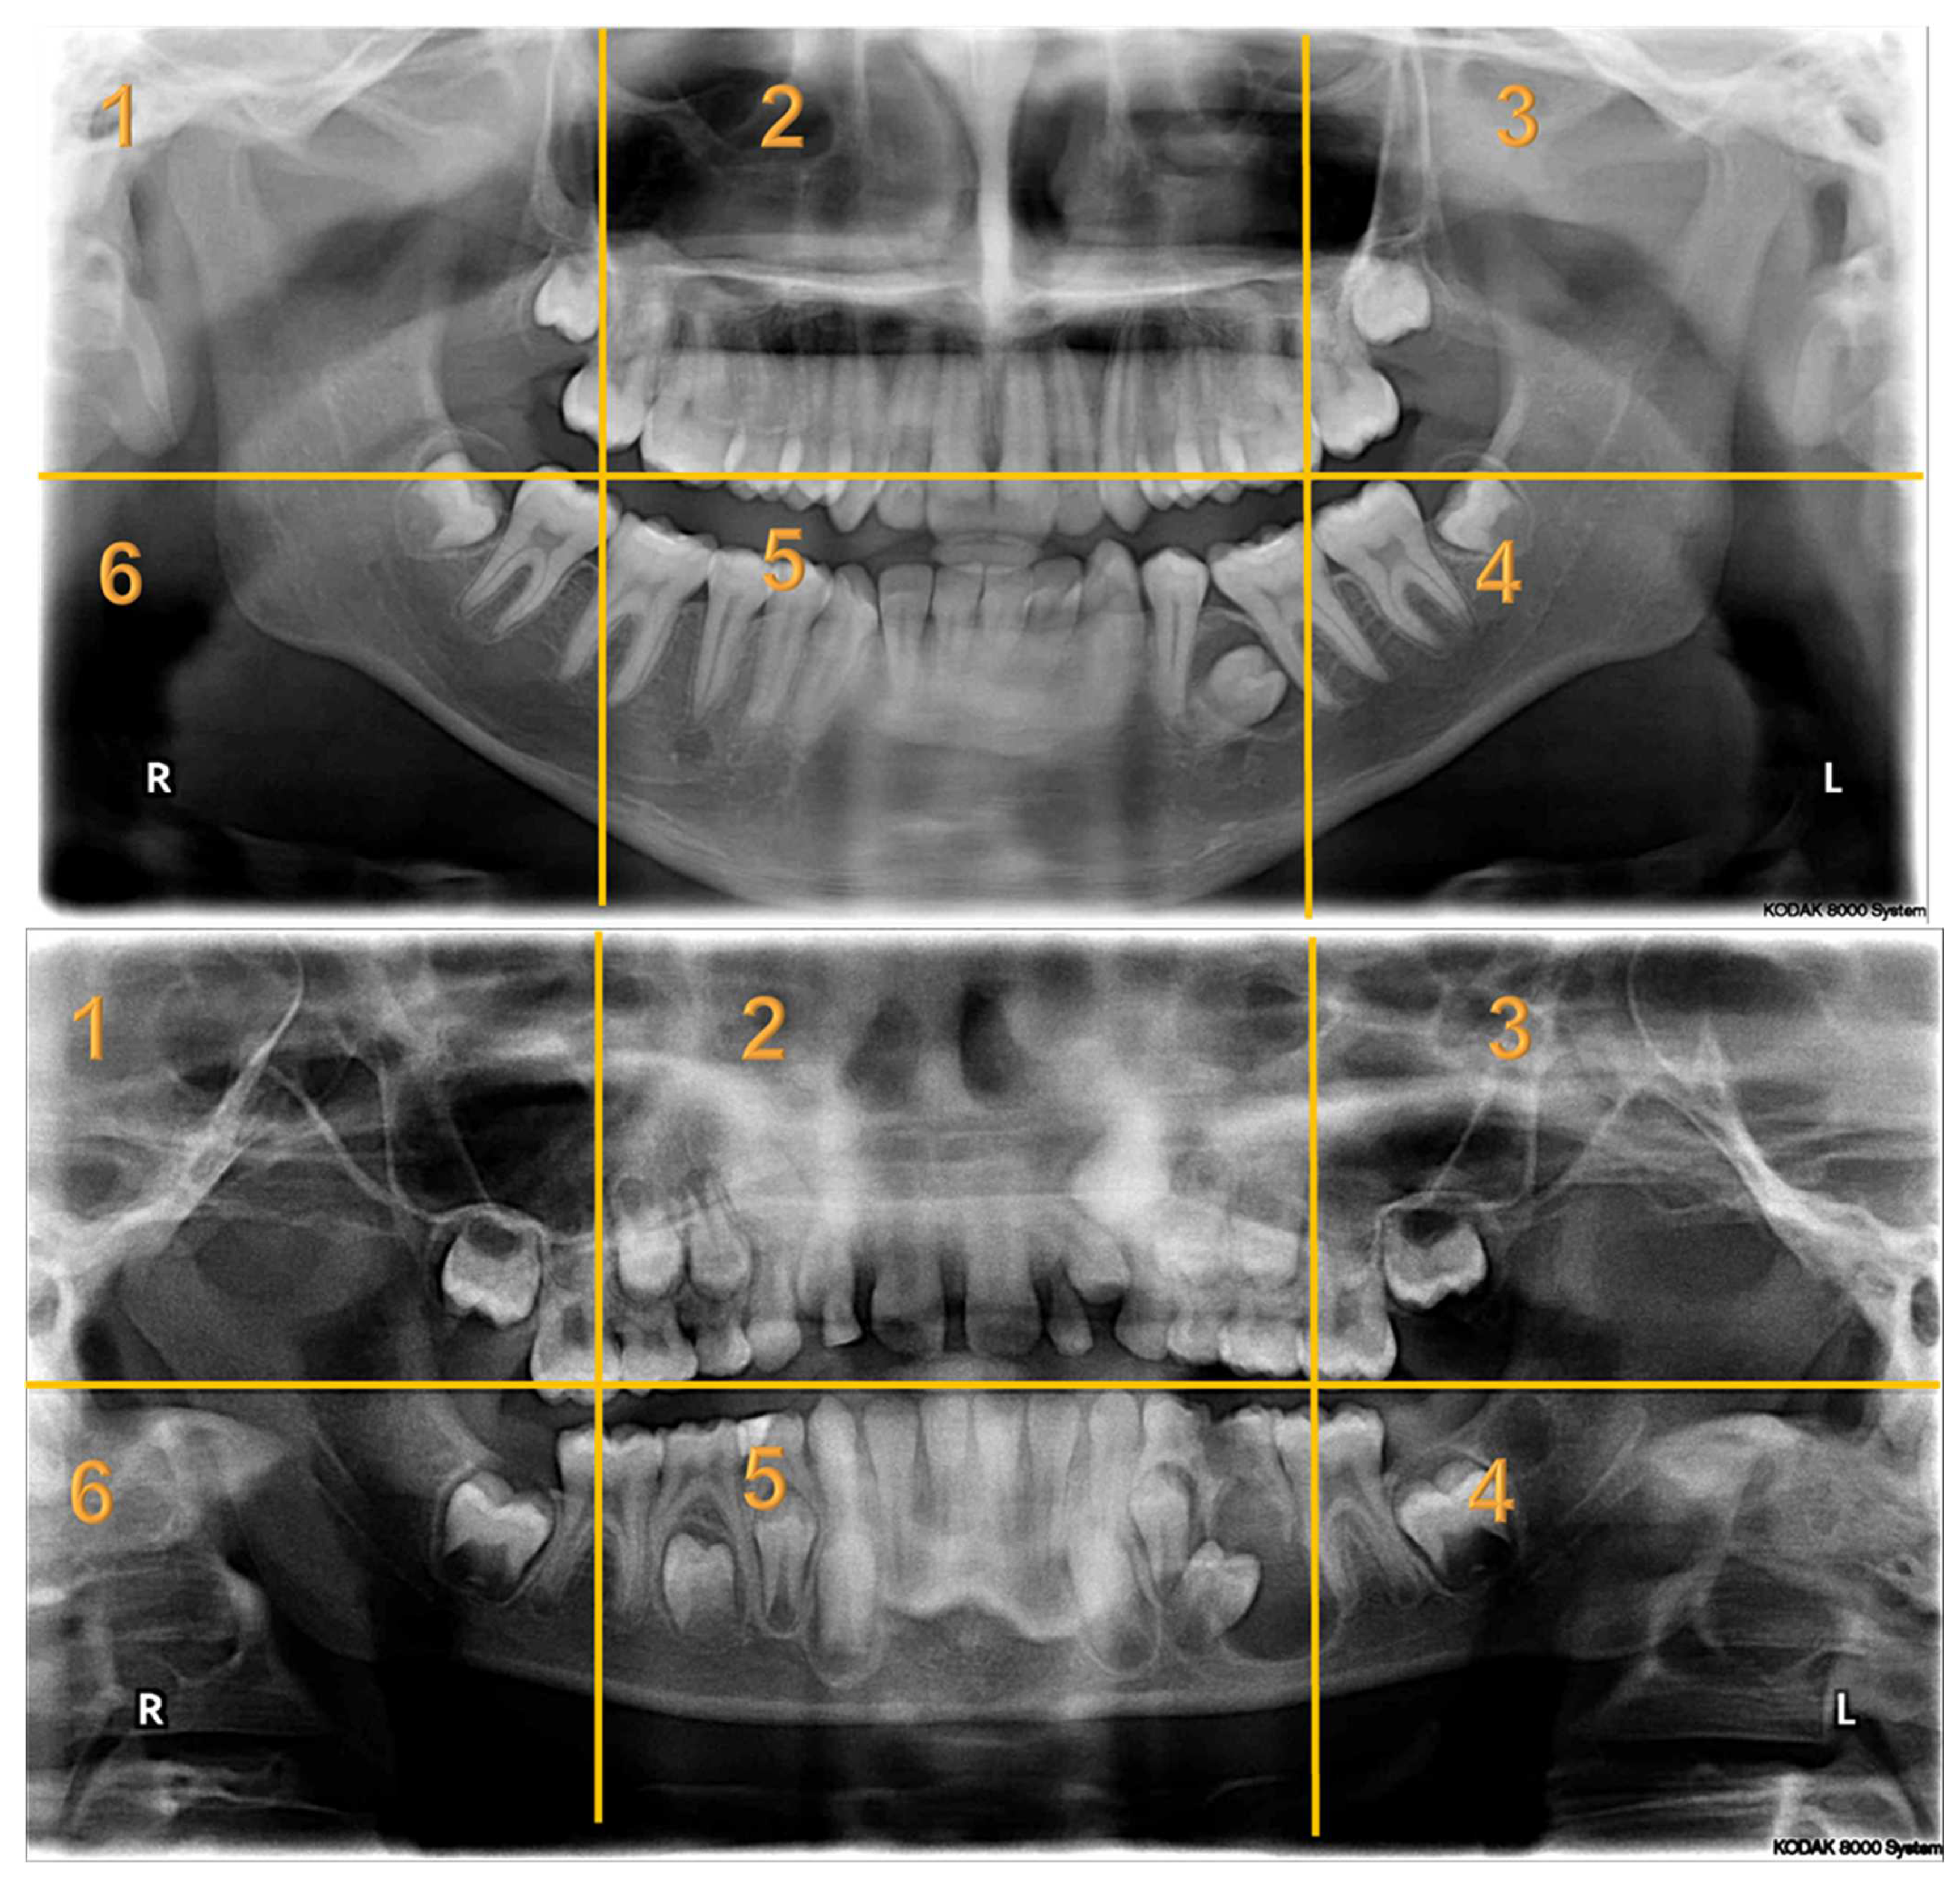

Seven panoramic radiographs (Appendix A) of pediatric dental patients aged between 6 and 16 years of age were selected from the electronic health system of KAUDH, based on their quality. Case selection mandated the presence of at least one bony lesion. A panel of experts from KAUDH, including three pediatric dentists and an oral radiologist, reviewed the selected cases to ensure that the radiographs were of good quality. All the images used in the study underwent no manipulation. The type of lesion was recorded for each patient and confirmed by their dental records. All identifying data were removed and a de-identified serial number was assigned to each case. The panoramic radiographs in this study presented a wide variety of abnormalities that included deviated nasal septum and enlarged nasal conchae; fibrous dysplasia; regional odontodysplasia or ghost teeth; dentigerous cysts; odontogenic keratocysts; enlarged dental follicle; missing, impacted, and rudimentary teeth; dilacerated roots; retained primary teeth; and periapical radiolucencies.

Appendix A. Radiographs Included in the Study